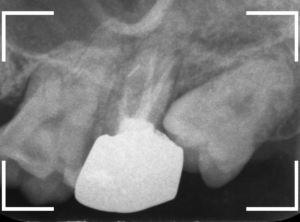

少し寄りかかってるケースですね。

寄りかかっているケースの中でも比較的抜きやすい生え方に見えますが、

若干、歯と骨の境界が不鮮明な上、下歯槽管という神経や血管が含まれる管(青いライン)に若干触れている可能性があります。

抜歯時に触れてしまう事で、顎や唇のしびれが生じたり、通常よりも多く出血するリスクがあるので、通常よりも抜きづらく、注意が必要な抜歯になります。

とはいえ、手前の歯が虫歯になりかかっている(赤いライン)可能性があるので、いつまでもこのままというわけにはいきません。

早めに抜歯する必要があります。